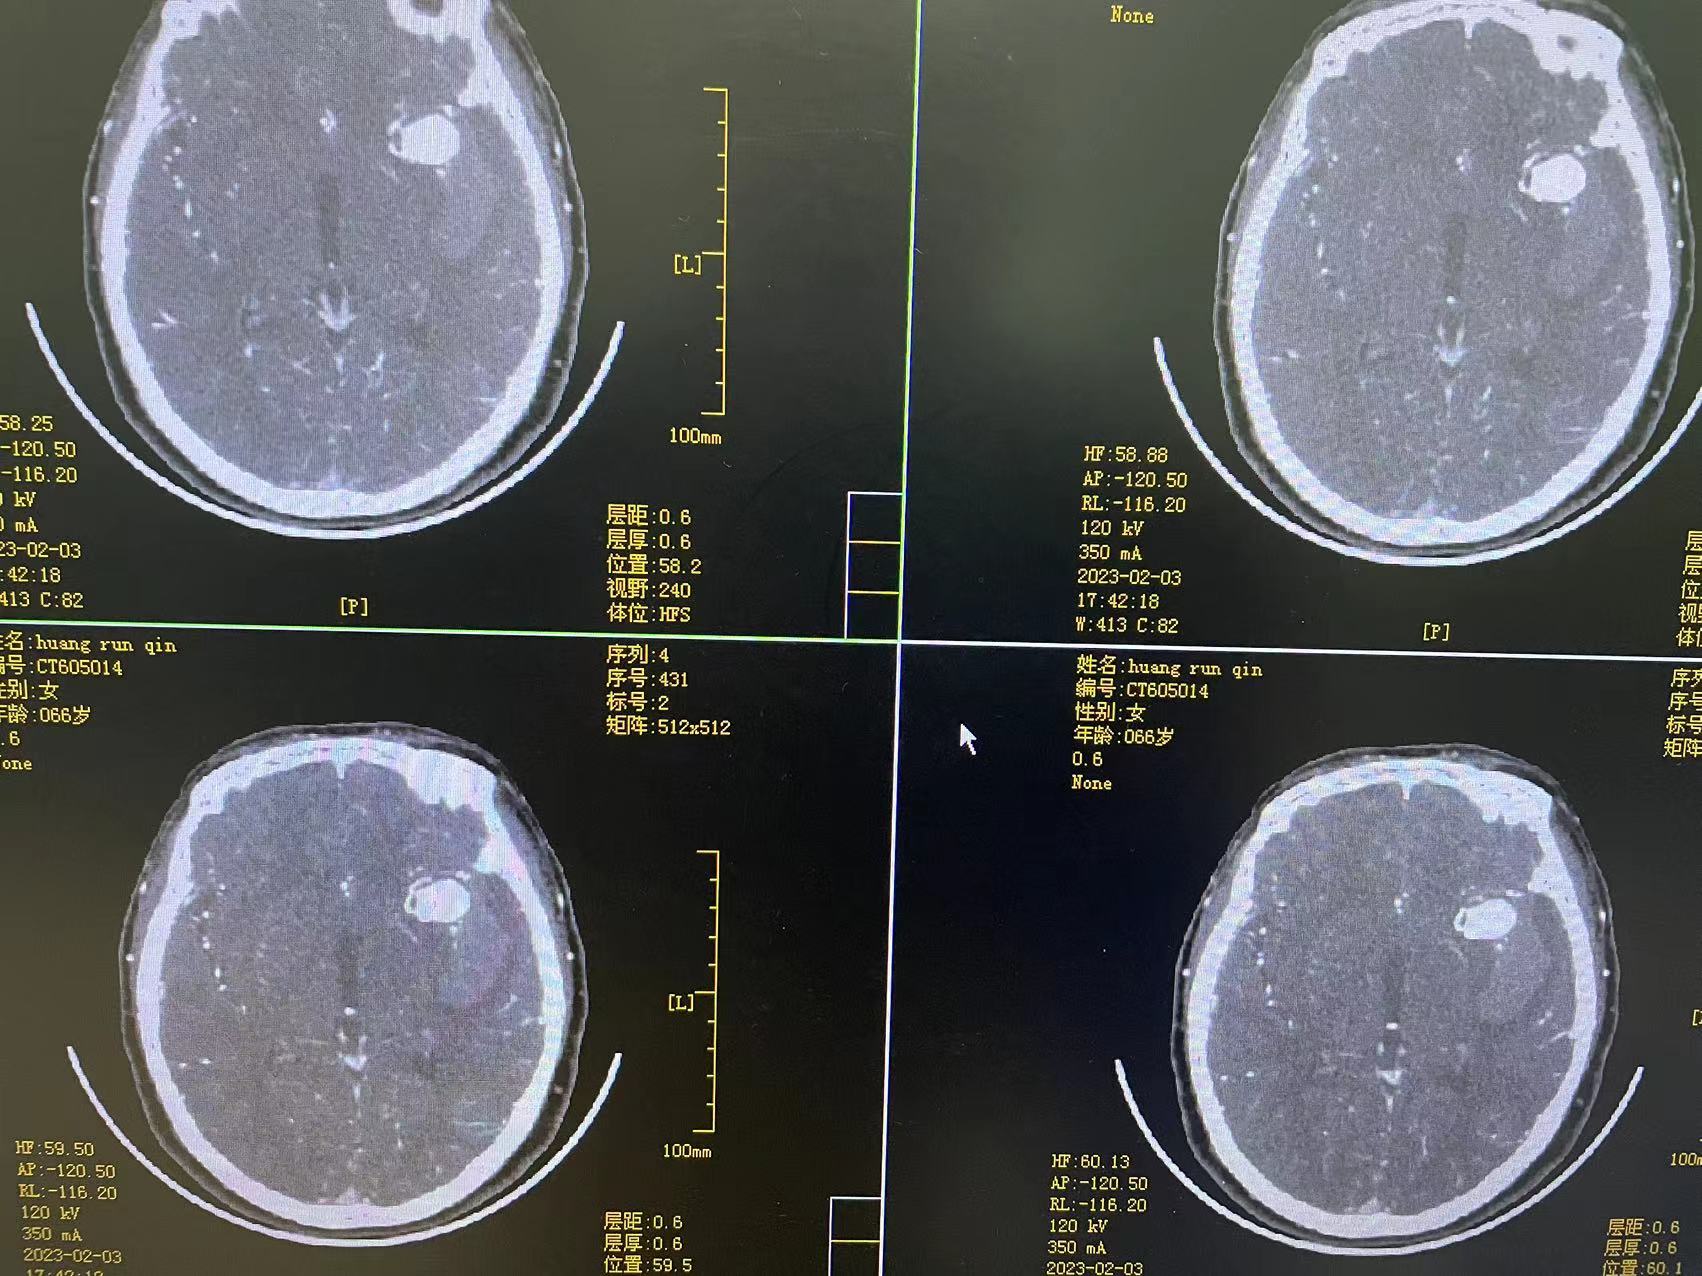

术后第三天

术后第五天